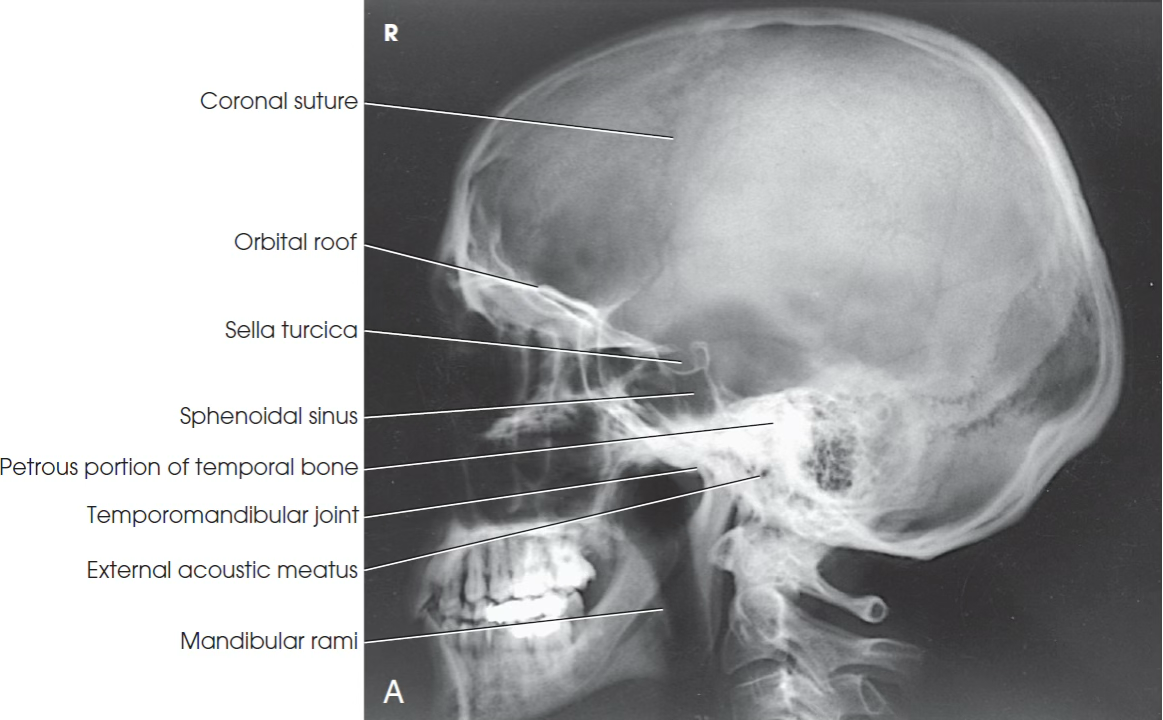

What view is this?

Lateral skull